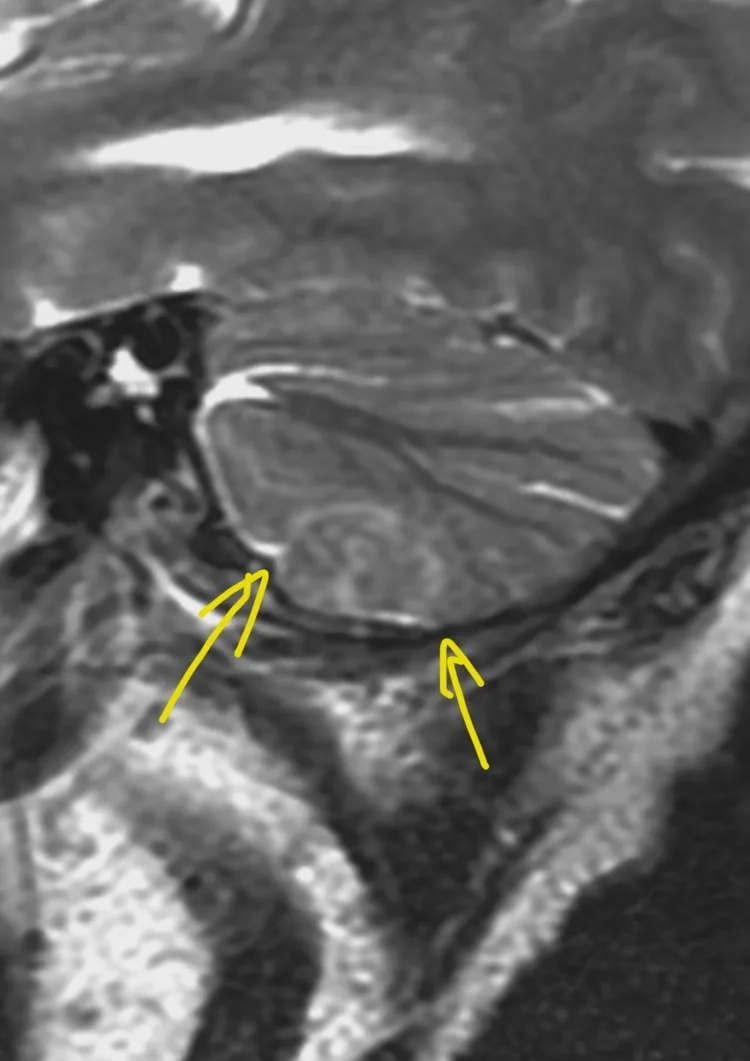

Наконец-то я увидел это воочию! Киста полости Верги, промежуточного паруса, осложнённая гидроцефалией. Из анамнеза: Низкое артериальнео давление, нарушение речи, затуманенное сознание, головная боль, головокружение, в 1989 году перенёс менингит.

А Вы видали такое? Я впервые вижу, раньше только читал в литературе.